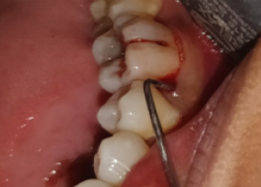

Half of Lower molar tooth along with diseased root removed & rest part is saved.

Post-OP Clinical View